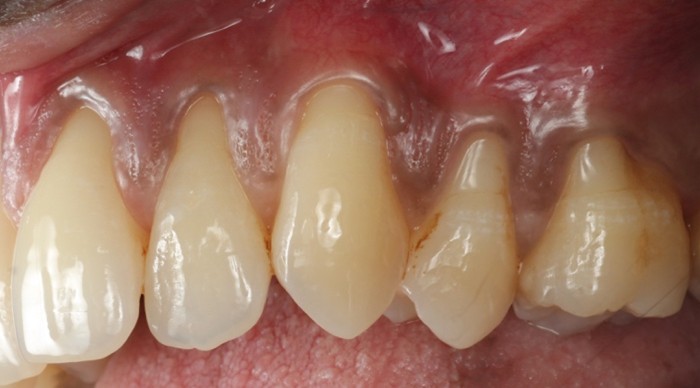

![]() | ![]() |

| Untreated severe gum disease | Gum disease treated and stabilised by Dr Halai |